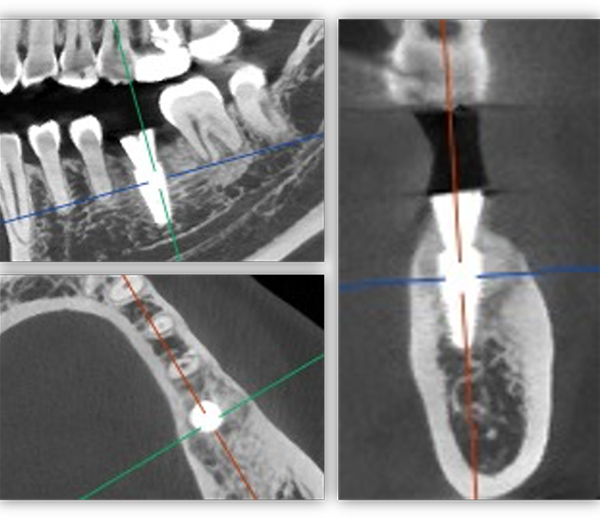

單顆是最常規的種植,不能因為常規就覺得簡單,治療時要追求小而精。從適應證把握到術式選擇,再到修復方式,術后的結果有沒有達到術前預期效果,都需要用心設計,事后復盤。這位患者是一位來自外地的年輕老師,有一顆6號牙需要種植。她只有在暑假兩個月的時間內可以來院,希望能在暑假期間完成治療。

為滿足患者的需求,我為她制訂了一個即拔即種、種植后早期負重的方案,把五個治療步驟縮減為三步。首次來院時,我為她完成了拔牙、種牙和安裝基臺,6周后來院拆線和取模,兩周后完成牙冠修復,也就是戴牙。整個治療周期僅8周,不到兩個月就完成了。

這個病例有一個特點,牙齒還在,但沒有功能。從表面看牙冠是完整的,但“金玉其外”,內部已經空了,牙根也爛穿了,無法咀嚼也失去了修復的條件,沒有保留價值。

6號牙也就是第一磨牙,是最早萌出的恒牙,比較容易齲壞。它雖然不在前牙美學區,不太容易影響容貌,但出于對美學的高要求,我在設計方案時也考慮了是按常規流程先拔牙,再備洞,還是以修復為導向,先按現有的牙冠來確定未來修復體的形狀,再去反推種植體植入的位置。后者對醫生來說難度更高一些,但更有利于復原天然牙的形態。

為保證這個方案的順利實施,我通過查閱文獻去印證方案的可行性,還為她建議了適合的種植體,原來三個月的骨結合時間能縮短為兩個月,種植體功不可沒。